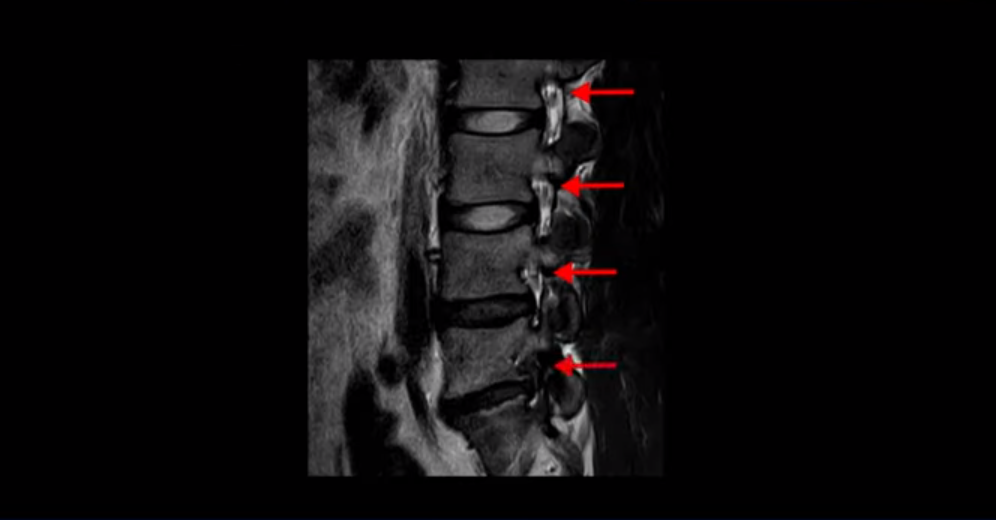

MRI를 보면 이분 5번 1번 디스크가 심하게 터져서 밀려 올라가 있습니다.

그런데 저희가 디스크 파열이 심하면 심할수록 치료가 잘 된다고 말씀 드리는 이유 첫 번째는 디스크가 심하게 터질수록 흡수가 더 잘 되기 때문입니다. 심하게 밀려나온 디스크 수핵은 우리 몸에서 이물질로 인식되기 때문에 우리 몸의 면역시스템이 녹여서 없애버립니다. 그래서 디스크 파열이 심하면 심할수록 흡수가 더 잘 됩니다.